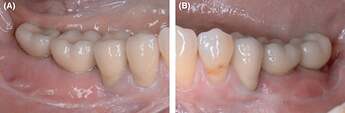

Figure 11.

Clinical situation after prosthetic treatment in the third and fourth quadrant. A, Clinical result on the allogeneic site after prosthetics. Fixed mucosa was increased by Kazanjian vestibuloplasty to 5‐6mm. B, Similar clinical situation on the autologous bone plates site

Figure 12.

Extracts from OPG: Radiological situation after prosthetic treatment. A, Allogeneic site with good integration of the implants and no crestal bone loss and well‐integrated relining layer. B, Autologous site showing good integration, no bone loss and well‐integrated relining layer on the autologous site